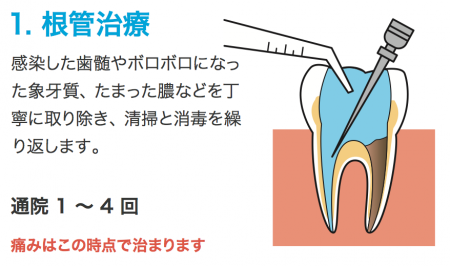

神経の管は人それぞれ複雑な構造になっているため念入りな処置が必要になります

抜髄処置の場合は、根管の清掃と洗浄は予定では2回行います。

痛みや違和感が消失しない場合は根管治療を繰り返します。